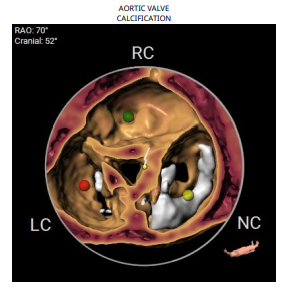

CT评估

1.瓣环及左室流出道。

2.主动脉瓣根部(左右瓣叶长度均超过冠脉高度)。

3.主动脉弓分析及瓣叶长度(最短弓距小于70mm)。

4.外周血管入路